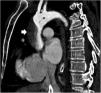

Paciente que ingresa en el hospital por síndrome coronario agudo complicado con comunicación interventricular (CIV). En un inicio se realiza tratamiento con angioplastia primaria y corrección quirúrgica de CIV. Durante el procedimiento desarrolló shock cardiogénico, con necesidad de balón de contrapulsación intraaórtico y ECMO-VA. A pesar del tratamiento hubo persistencia de CIV, por lo que se propone para trasplante cardiaco en centro de referencia. Previo a ello, se realiza angioTC con imagen compatible con disección de aorta ascendente (figs. 1 y 2), por lo que se desestima. Tras la revisión de imágenes en el centro trasplantador, se descarta disección tras valoración en ecocardiografía transesofágica del arco aórtico (fig. 3), considerando que la imagen se produce por confluencia de flujos de ECMO, lo que permite el trasplante.